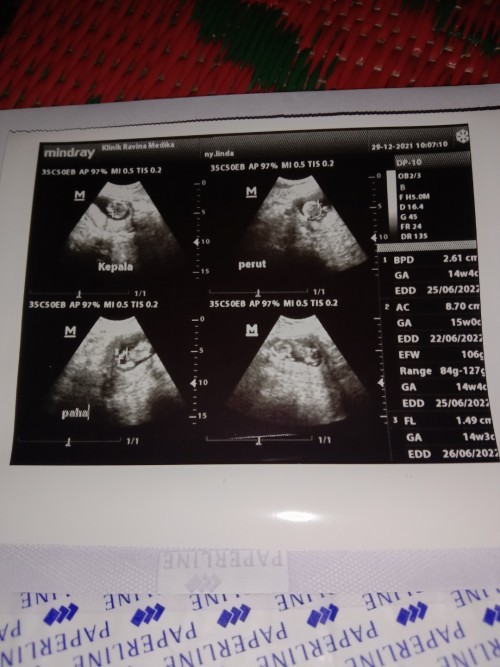

15 wk Alhamdulillah SDH aktif bergerak kata bidannya tp blm kerasa yah